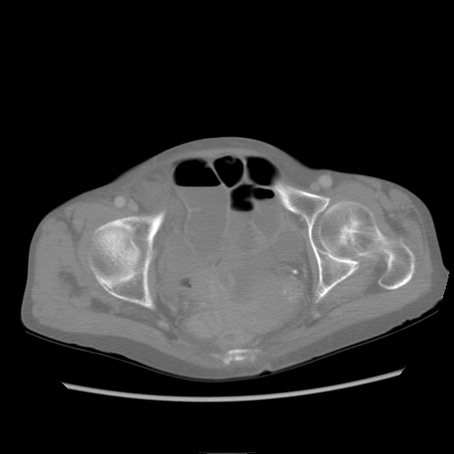

症例25(横断像)

【症例】80歳代女性

【主訴】胸のつかえ感

【現病歴】約9時間前に食後から胸のつかえた感じあり、嘔吐あり、来院。

【既往歴】胃癌(全摘)、胆摘、虫垂炎

【身体所見】心窩部に圧痛あり、反跳痛なし。

【データ】WBC 5700、CRP 0.05